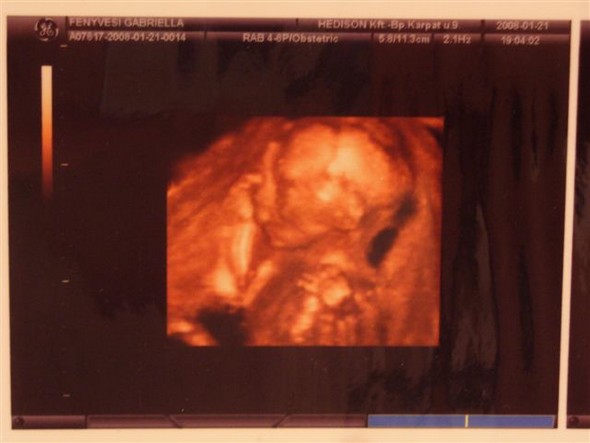

Gabi várunk nagyon az uh-s hírekkel(az érzéseim egyébként azt súgják,hogy kisfiú